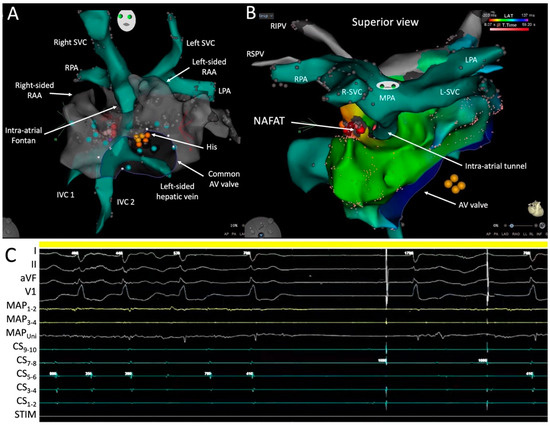

A crucial aspect of the procedure involves the acquisition, segmentation, and annotation of three-dimensional images, usually obtained from preprocedural computed tomography (CT) scans or cardiac magnetic resonance (CMR) imaging. This facilitates the visualization of anatomic intricacies and serves as a navigational guide for directing the RMN-guided ablation catheter. Figure 4 presents a static view of the patient’s cardiac anatomy that was imported into the 3D-electroanatomic system and semi-automatically segmented utilizing the CARTOSEG CT module (Biosense Webster). A three-dimensional rotational view is provided in Supplementary Video S1.

5.7. Mapping and Ablation in the Pulmonary Venous Atrium

Once in the PVA, a fast anatomical map was created to provide a geometric shell and localize the AV conduction system. This step is vital in patients who have displaced or difficult-to-predict locations of the AV node to avoid inadvertent damage during ablation. Figure 9A shows the position of the His signal recorded along the superior border of the common AV valve. The relationship between the systemic venous atrium and PVA could be appreciated. The intra-atrial conduit is surrounded by the PVA and pierces its roof before anastomosing with the main PA (MPA).

During single atrial extra-stimulus testing at a drive train of 600 ms, the clinical tachycardia, which had a cycle length of 440 ms, was easily induced. Activation and entrainment mapping revealed a non-automatic focal atrial tachycardia (NAFAT) on the roof of the PVA, adjacent and to the right of the intra-atrial tunnel alongside scar tissue (Figure 9B). At this site, catheter ablation resulted in acceleration of the tachycardia followed by slight slowing before termination (Figure 9C). A propagation map of the tachycardia is shown in Supplementary Video S2. Tachycardia was no longer inducible post ablation and the patient has remained arrhythmia-free since. Ideal procedural endpoints include termination of all focal atrial tachycardias during ablation, demonstration of bidirectional block across linear ablation lesions if relevant, and non-inducibility of any atrial tachycardia.

Figure 4. CT scan images segmented and imported into a 3D-electroanatomic mapping system. R-SVC and L-SVC denote right and left superior vena cavae; RSPV, right superior pulmonary vein; RPA, right pulmonary artery; RAA, right atrial appendage; RIPV, right inferior pulmonary vein; PVA, pulmonary venous atrium; DORV, double-outlet right ventricle; IVC, inferior vena cava.

Figure 9. Mapping and ablation in the pulmonary venous atrium. Shown in Panels (A,B) are 3D views of electroanatomic maps. R- and L-SVC denote right and left superior vena cavae; RPA and LPA, right and left pulmonary arteries; RAA, right atrial appendage; AV, atrioventricular; IVC, inferior vena cava; RIPV, right inferior pulmonary vein; RSPV, right superior pulmonary vein; MPA, main pulmonary artery; NAFAT, non-automatic focal atrial tachycardia. Shown in the tracing in Panel (C) are surface ECG leads I, II, aVF, and V1; intracardiac recordings from the distal (MAP1-2) to proximal (MAP3-4) and unipolar (MAPUni) mapping catheter; and the proximal (CS9-10) to distal (CS1-2) coronary sinus catheter. STIM denotes the stimulation channel.